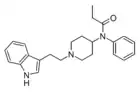

| Indolylethylfentanyl | artificial | H | (CH2)5-4-N(COCH2CH3)C6H5 | N-[1-[2-(1H-indol-3-yl)ethyl]piperidin-4-yl]-N-phenylpropanamide | 58399-46-5 | |